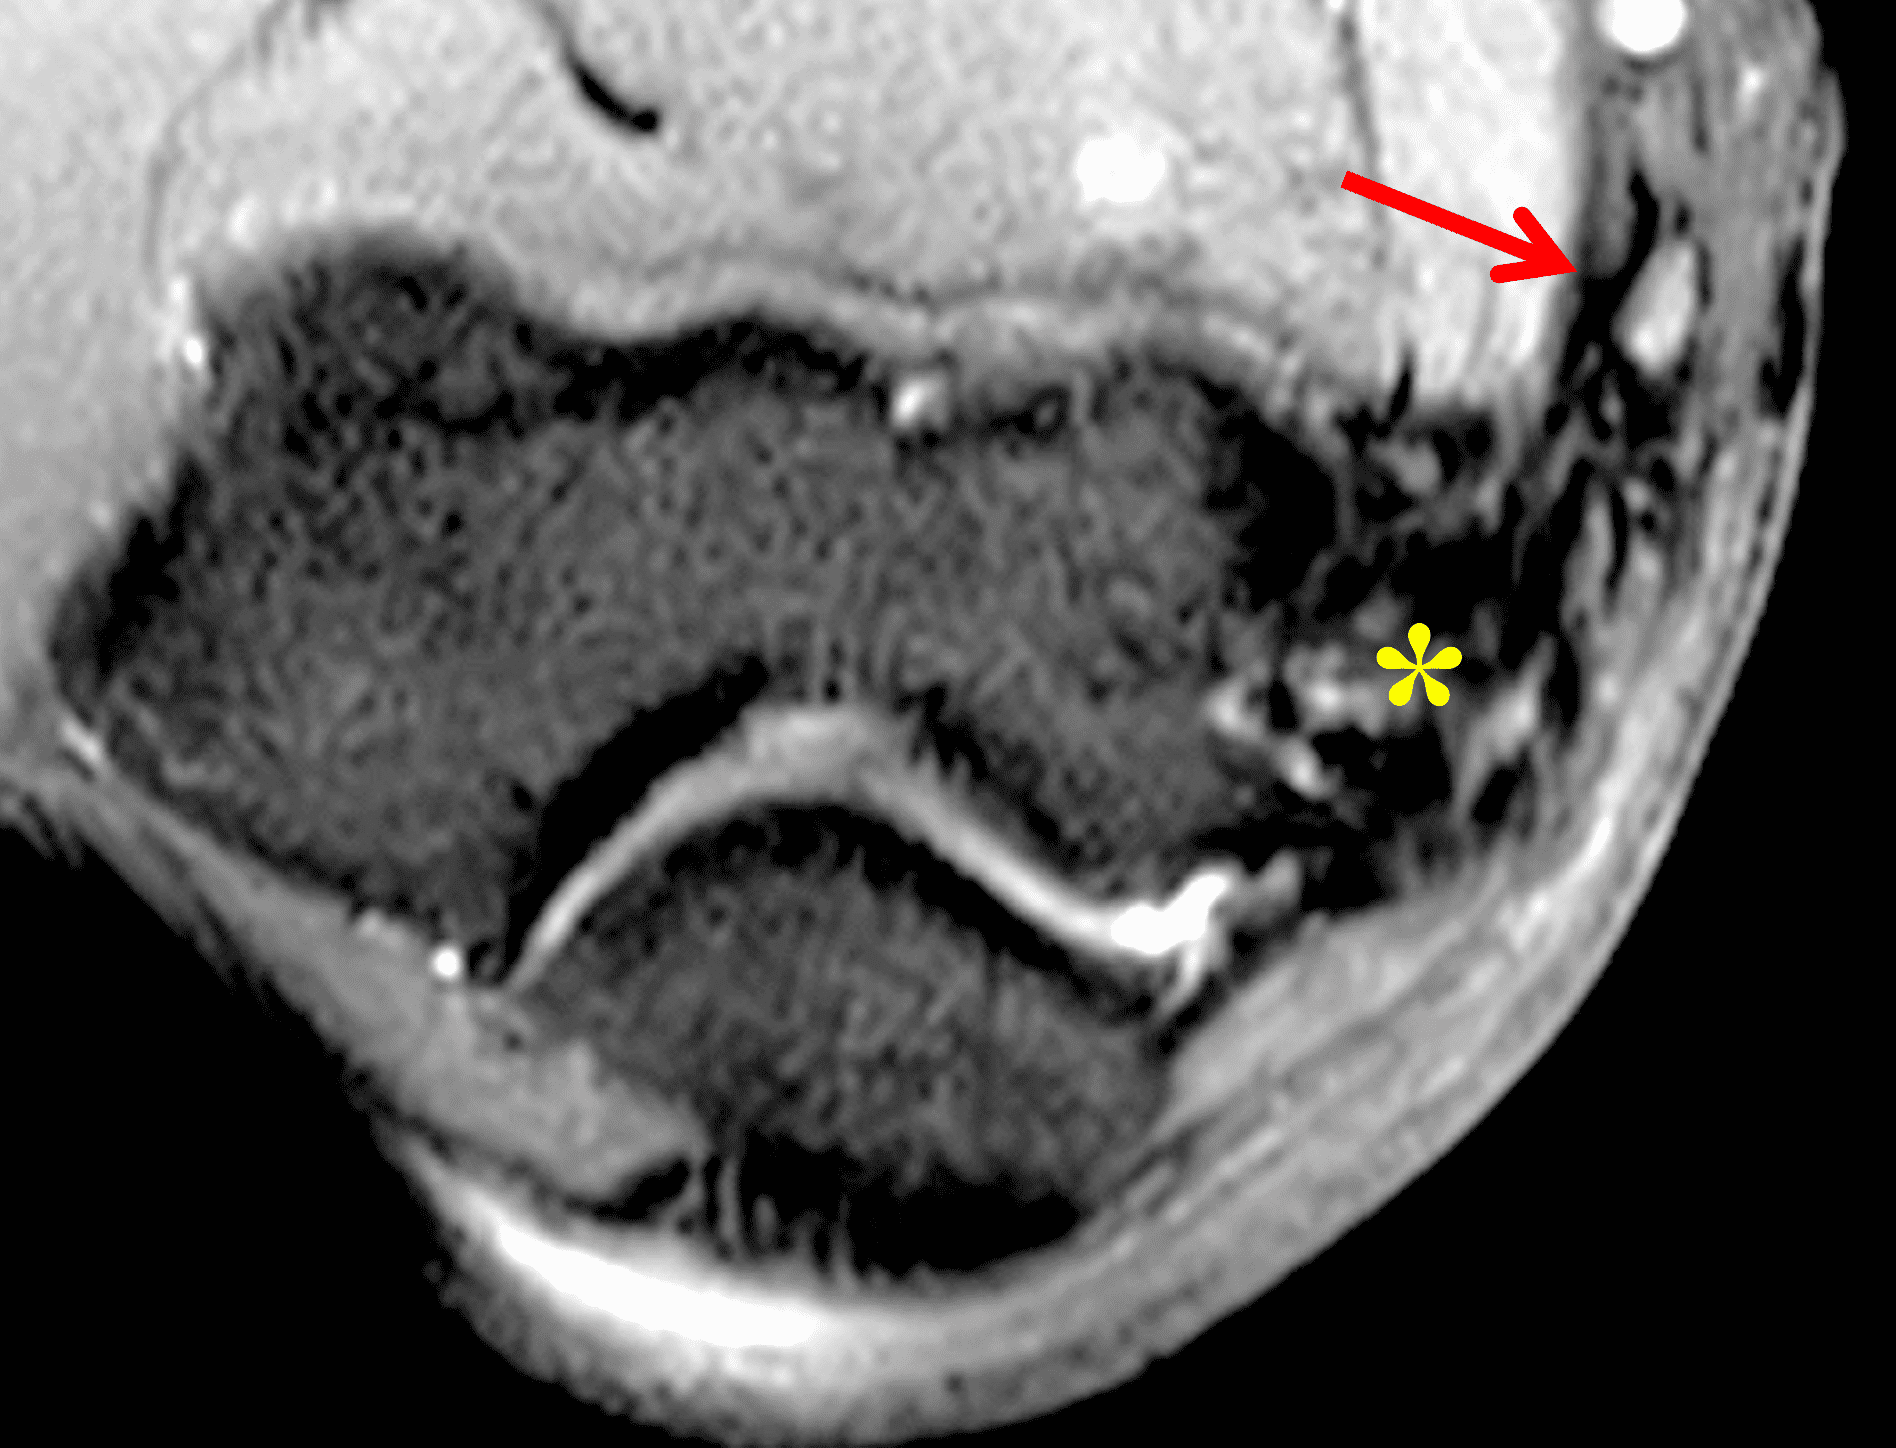

A 55-year-old man complains of pain, numbness, and tingling in the ulnar aspect of the hand and in the small and ring fingers. The symptoms are more severe with elbow flexion and during sleep. He has no muscle weakness or history of trauma. Axial T1-weighted (1A, 1B) and fat-suppressed, fluid-sensitive (1C, 1D) images are shown. What are the findings? What is your diagnosis?

Figure 2: At the level of the cubital tunnel (2A and 2C), identifiable by the thin cubital tunnel retinaculum (yellow arrow), the ulnar nerve (red arrow) is focally enlarged and hyperintense compared to the nerve more distally (2B and 2D), where it lies between the two heads of the flexor carpi ulnaris muscle (asterisks). No soft tissue mass is present.